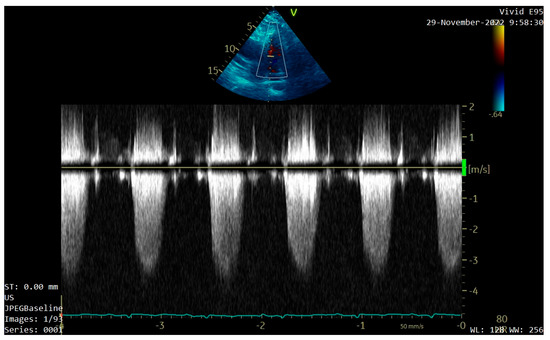

A transthoracic echocardiography (TTE) was performed. It showed a round 25/30 mm, 6.5 cm2 intracardiac mass attached to the right ventricle outflow tract (RVOT) wall by a 5 mm thick pedunculus (Figure 1a), which prolabated through the pulmonary valve in systole, thus causing severe obstruction at this level with a maximum gradient of 70 mmHg (Figure 1b and Figure 2). The pulmonary valve itself presented no structural abnormalities, but the right ventricle was dilated (50 mm at the base) with a slightly decreased systolic function (TAPSE = 15 mm), a moderate tricuspid regurgitation and paradoxical interventricular septum motion being also observed due to right ventricular pressure overload. The left ventricle was not dilated and had a preserved systolic function, and only a mild mitral regurgitation was noted.

Figure 1. Transthoracic echocardiography (TTE) showing: (a) a round intracardiac mass attached to the right ventricle outflow tract (RVOT) wall by a pedunculus (white arrow); (b) turbulent flow on Color Doppler caused by the tumor’s severe obstruction of the RVOT (white arrow).

Figure 2. TTE Continuous Wave Doppler showing severe RVOT obstruction.